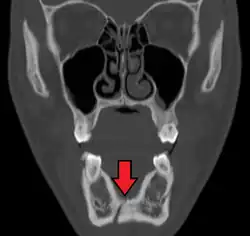

| |

| 3D computed tomographic image of a mandible fracture in two places. One is a displaced right angle fracture and the other is a left parasymphyseal fracture. | |

Mandibular fractures are typically the result of trauma.[1] This can include a fall onto the chin or a hit from the side.[1] Rarely they may be due to osteonecrosis or tumors in the bone.[1] The most common area of fracture is at the condyle (36%), body (21%), angle (20%) and symphysis (14%).[1] Rarely the fracture may occur at the ramus (3%) or coronoid process (2%). While a diagnosis can occasionally be made with plain X-ray, modern CT scans are more accurate.[1]

Computed tomography is the most sensitive and specific of the imaging techniques. The facial bones can be visualized as slices through the skeletal in either the axial, coronal or sagittal planes. Images can be reconstructed into a 3-dimensional view, to give a better sense of the displacement of various fragments. 3D reconstruction, however, can mask smaller fractures owing to volume averaging, scatter artifact and surrounding structures simply blocking the view of underlying areas.